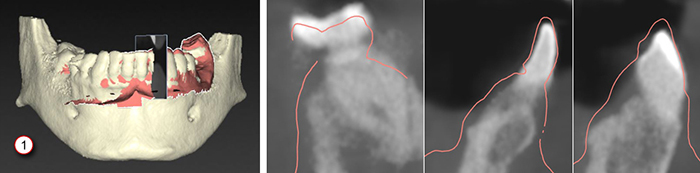

12. On the Check result page of the wizard, check whether the patient model and the dental scan are correctly aligned. It is possible to show or hide the dental scan by toggling the visibility icon of the objects.

13. Verify that the automatic alignment is correct by scrolling through the reslices. The outline of the aligned dental scan (default pink color) must accurately correspond to the occlusal information of the teeth within the (CB)CT scan. It is the clinician’s responsibility to make sure this step is correct.

1. Incorrect alignment

2. Correct alignment